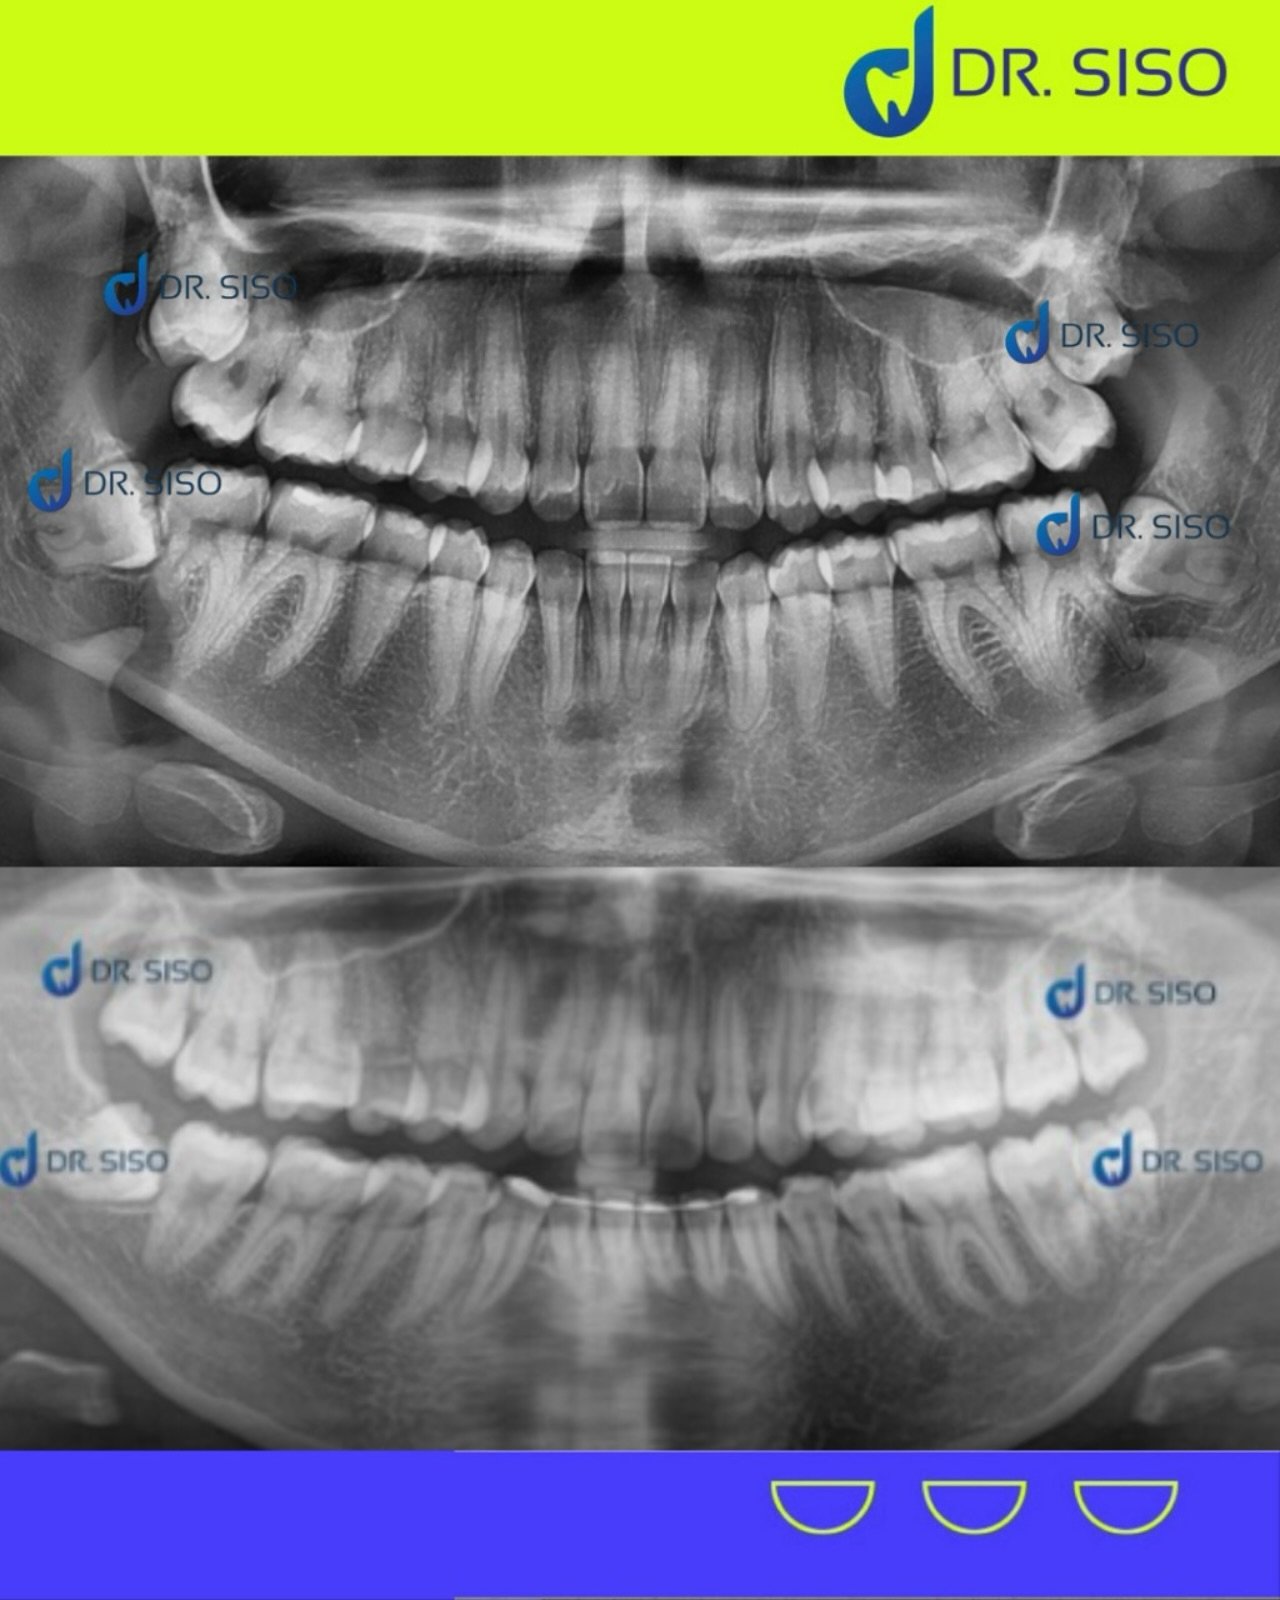

Sim, em muitos casos. Mesmo sem dor, o siso pode estar mal posicionado, pressionando outros dentes, causando reabsorção óssea ou prejudicando a mordida. A avaliação clínica e radiográfica é essencial para decidir com segurança.